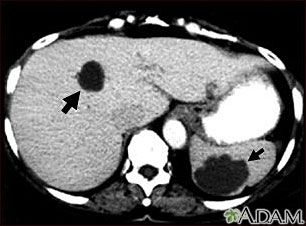

Liver and spleen cysts - CT scan

This abdominal CT scan shows multiple cysts in the liver and spleen. Note the dark circular cyst in the liver (left side of screen) and the large, irregular, circular cyst in the spleen (bottom, right side of screen).